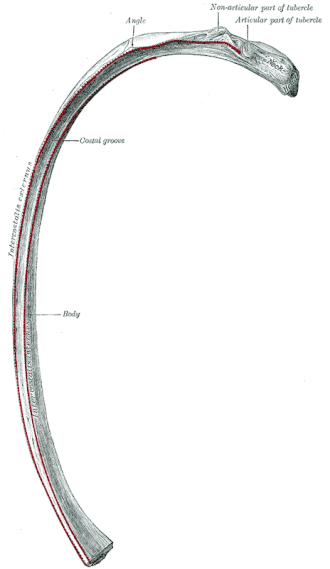

![]() Detaliul unei singure coaste umane | |

Părțile unei coaste includ capul, gâtul, corpul (sau „arborele”), tuberculul și unghiul.

capul coastei se află lângă o vertebră. Coastele se conectează la vertebre cu două articulații costovertebrale, una pe cap și una pe gât. Capul coastei are o regiune superioară și o regiune articulată inferioară, separată de o creastă. Acestea se articulează cu superior și fațeta costală inferioară de pe vertebrele de legătură.[3] Creasta conferă atașament la ligamentul intra-articulat care unește coasta la vertebra aceluiași număr, la discul intervertebral. Un alt ligament, ligament radiat se alătură capului coastei atât corpului vertebrei superioare, cât și corpului vertebrei inferioare. Partea de mijloc mai mică a ligamentului se conectează la discul intervertebral. Această articulație plană este cunoscută sub numele de articularea capului coastei.

Cealaltă articulație costovertebrală este cea dintre tuberculul de pe gât și procesul transversal al vertebrei toracice de îmbinare a aceluiași număr de coastă, iar acest lucru este cunoscut sub numele de articulația costotransversă. Ligamentul costotransvers superior se atașează de la fațeta non-articulară a tuberculului la procesul transversal al vertebrei.

Gâtul coastei este o parte aplatizată care se întinde lateral de la cap. Gâtul are aproximativ 3 cm lungime. Suprafața sa anterioară este plană și netedă, în timp ce posteriorul său este perforat de numeroase foramina și suprafața sa aspră, pentru a da atașament la ligamentul gâtului. Marginea sa superioară prezintă o creasta aspră („crista colli costae”) pentru atașarea anterior ligamentcototransvers; bordura sa inferioară este rotunjită.

Un tubercul de coastă, pe suprafața posterioară a gâtului coastei, are două fațete (suprafețe) una articulată și una nepultifică. Fațeta articulară, este mică și ovală și este cea mai joasă și mai medială dintre cele două, și se conectează la fațeta costală transversală de pe vertebra toracică a aceluiași număr de coaste.[3] Fațeta transversală costală se află la sfârșitul procesului transversal al celei inferioare a celor două vertebre la care este conectat capul. Porțiunea non-articulară este o elevație brută și oferă atașament la ligamentul tuberculului. Tuberculul este mult mai proeminent în coastele superioare decât în coastele inferioare.